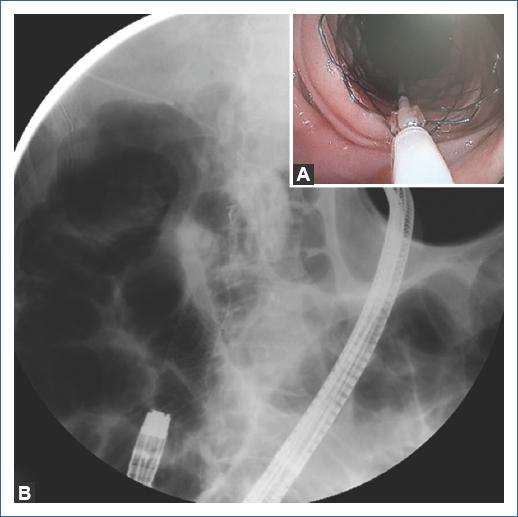

First, a colonoscope (190 Olympus Medical Systems, Tokyo Japan) was passed up to the choledochojejunostomy, which was found kinked and angulated. Therefore, the colonoscope was withdrawn and an enteroscope (EVIS EXERA II [SIF-Q180], Olympus Medical Systems, Tokyo Japan) was passed until the kinked choledochojejunostomy. Second, a hydrophilic Guidewire (0.035 mm Jagwire Revolution High Performance Guidewire, Boston Scientific Corp) was introduced percutaneously into the biliary tree under transabdominal ultrasound assistance to access the afferent limb (Fig. 1), and the guidewire was recovered with the enteroscope (Fig. 2). Third, the enteroscope holding the guidewire was withdrawn and interchanged into a stent-loaded colonoscope. Finally, the colonoscope holding the guidewire was introduced and an enteral uncovered self-expandable metal WallFlex Duodenal Stent, Boston Scientific Corp (22 mm × 60 mm) was successfully deployed at the site of the obstruction (Fig. 3). The schematic representation of the technique is described in figure 4. The patients evolution was satisfactory and was discharged 48 h after the procedure.

Figura 3 A: endoscopic deployment of enteral metallic stent with a colonoscope. B: enteral stent in correct position.